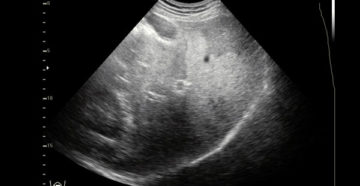

Жировой гепатоз Поражение печени в современных вредных условиях и богатой стрессами жизни не такое уж…